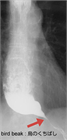

1. HRMに加えて、食道バリウム造影で経時的に食道内のバリウム貯留の程度を評価するTimed barium esophagogram(TBE)は診断に有用である。